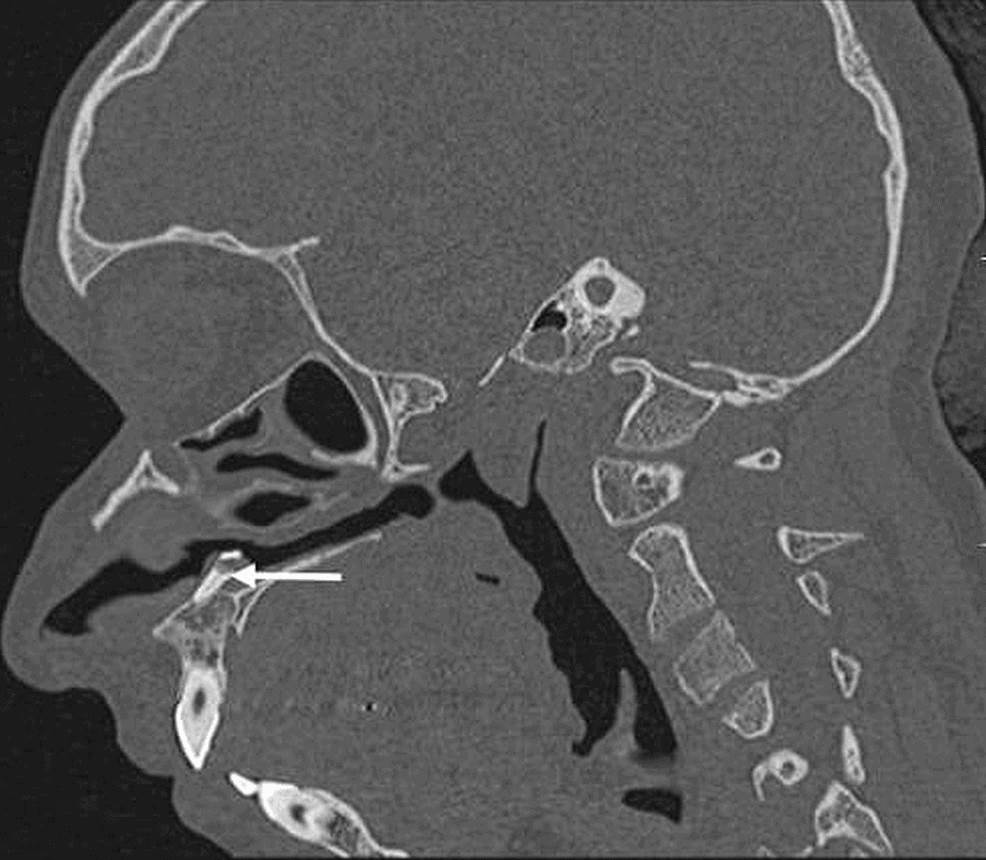

Raro de diente ectópico intranasal en mujer joven se registra en la literatura  Imagen coronal que muestra una estructura similar a un hueso (flecha blanca) incrustada en el paladar duro que se extiende hacia la cavidad nasal izquierda. Raro de diente ectópico intranasal en mujer joven se registra en la literatura  Tomografía computarizada axial que muestra un diente ectópico en la cavidad nasal izquierda rodeado de tejido blando (flecha blanca). Raro de diente ectópico intranasal en mujer joven se registra en la literatura  La radiografía simple muestra la estructura radiopaca en la fosa nasal izquierda, incrustada en el paladar duro (flecha blanca). Raro de diente ectópico intranasal en mujer joven se registra en la literatura  Imagen sagital que muestra la extensión completa de un diente intranasal (flecha blanca), que se encuentra incrustado en el paladar duro.

Raro de diente ectópico intranasal en mujer joven se registra en la literatura  Imagen sagital que muestra la extensión completa de un diente intranasal (flecha blanca), que se encuentra incrustado en el paladar duro.

Recalcaron además la importancia de las imágenes radiológicas que ayudaron en el diagnóstico de un diente ectópico.